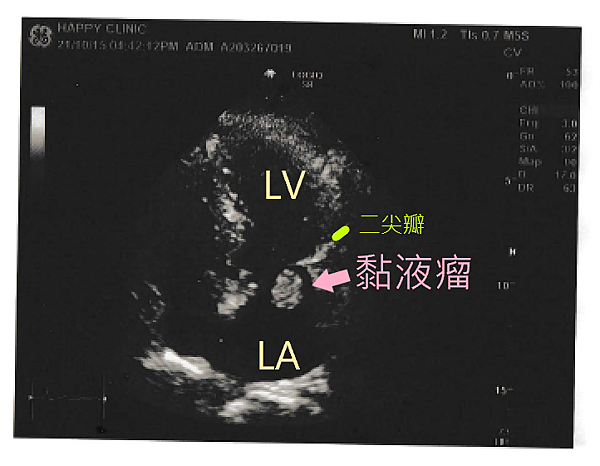

案例分享 - 黏液瘤

巫女士,80歲,活動力很強,每天例行出門採買與運動,因家中無電梯,每天也自行爬樓梯回住處。

2021年10月至天行健診所進行例行性全身健康檢查,其中心電圖檢查發現胸前導程V1—V6呈現倒置T波、肢體導程II, III, aVf呈現扁平T波,代表廣泛前壁及下壁心肌缺血。心臟科王復蘇醫師立即安排心臟超音波檢查,意外在患者的左心房接近二尖瓣位置發現2公分的黏液瘤(myxoma)。

王醫師立刻開立轉診單請患者至大型醫院進行檢查,患者至醫學中心就診,立刻被安排住院檢查,包括心導管、抽血與影像學等檢查,長達4-5天,經過院內相關科室討論,確認患者左心房為腫瘤,須立即接受開心手術將其取出。

隔日,患者經6-7小時的開心手術,順利取出心臟腫瘤,經病理切片檢查確定腫瘤為良性,無轉移現象,僅留下15公分傷口。患者術後配合院內安排,進行肺活量訓練、與藥物、營養品補充,每日服用抗凝血劑、降壓藥,與促進傷口修復專用保養品,至今3個月恢復狀況良好。

巫女士術前未有任何胸悶、呼吸困難等症狀,活動力十足,好在家人每年安排例行性健康檢查,及時發現心臟腫瘤,並接受妥善治療。王復蘇醫師表示,黏液瘤雖然是良性腫瘤,但若長在二尖瓣膜,容易引起細菌滋生引發心內膜炎,甚至心臟衰竭與心因性猝死症,須格外小心謹慎。